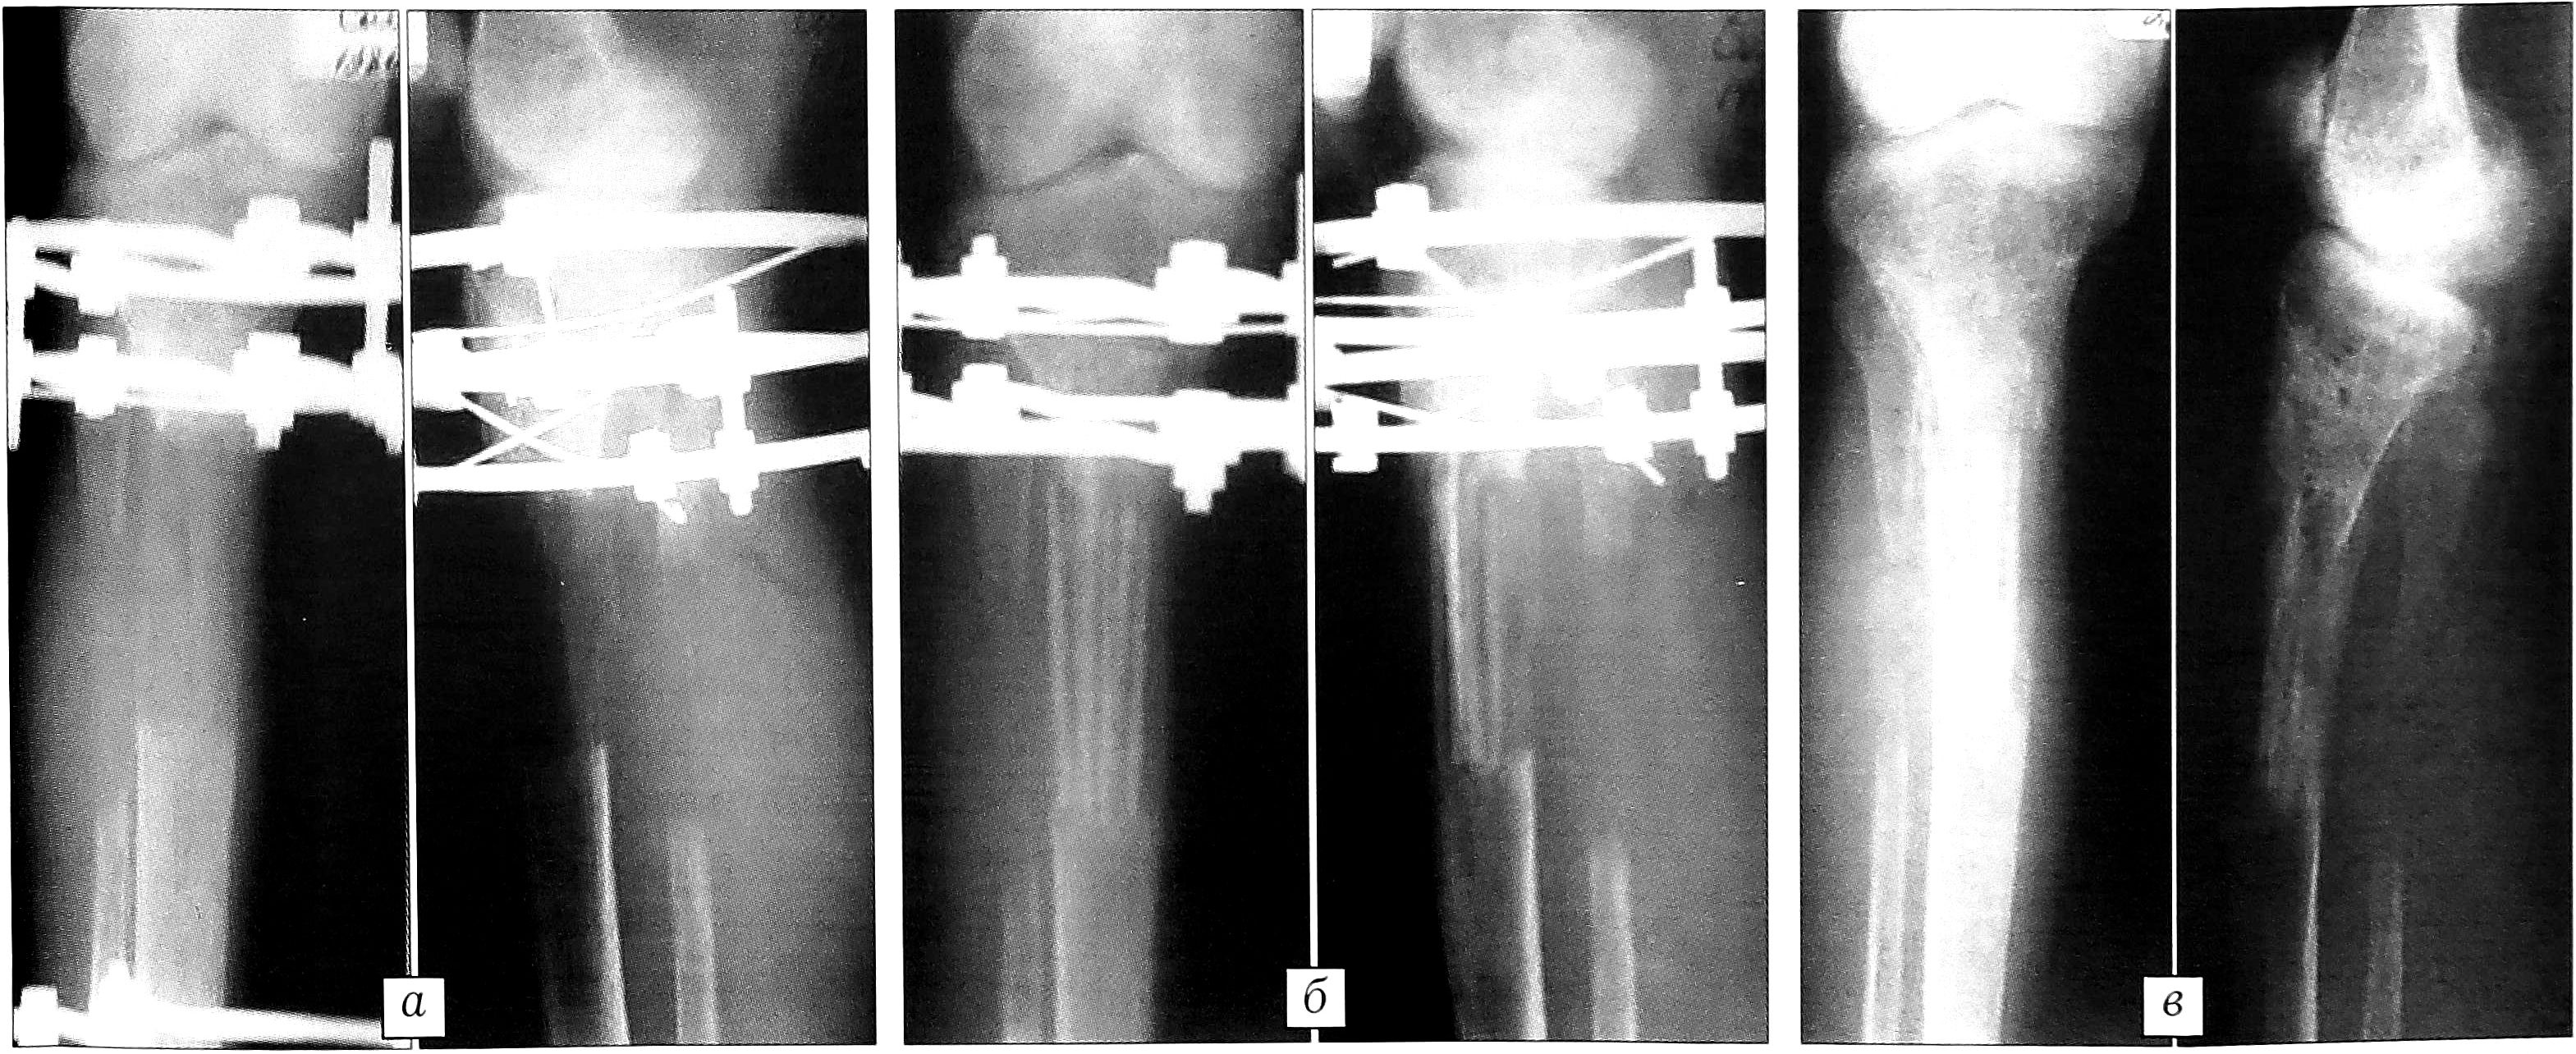

Аллопластика дистракционного регенерата «Перфоостом» была выполнена у 6 больных (витамин-В-резистентный рахит — 3 пациента, ахондроплазия, гипохондроплазия, врожденное укорочение нижней конечности — по одному больному) (рис. 6). Показанием к применению «Перфооста» являлась слабая минерализация регенерата и необходимость ускорения в нем процессов костеобразования. Для этого изготавливались аллоимплантаты с высокой степенью деминерализации.

Рис. 6. Рентгенограммы больной С. 16 лет. Диагноз: витамин-D-резистентный рахит. а — слабая минерализация регенерата правой большеберцовой кости в аппарате Илизарова; б — после аллопластики по регенерату «Перфоостом» с высокой степенью деминерализации; в — через 5 мес после аллопластики.